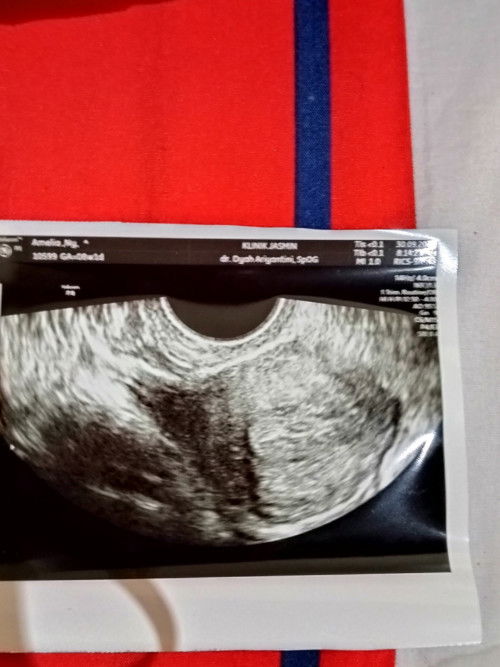

Ingin tahu hasil USG😌

Ini hasilnya bagaimana ya masih bingung,apakah tanda kehamilan,apakah penebalan dinding rahim?#seriusnanya #bantusharing

nanti kalau usg lagi tanyain apa yang belum jelas. keluhan semua utarain. emang itu berapa minggu